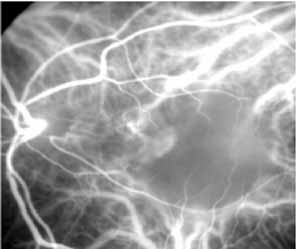

MULTIFOCAL CHOROIDITIS

Most promising in this category of inflammatory choroidopathies is a better detection and understanding of the lesions of multifocal choroiditis. Multiple large, scattered, hypofluorescent spots are seen on ICG angiography, particularly in the later phases of the angiogram69 (Fig. 18). These lesions are not evident either on clinical examination or on fluorescein angiography. In addition to having these larger hypofluorescent lesions, patients with multifocal choroiditis have smaller dot-like lesions and hyperfluorescent foci that do not correlate with lesions seen clinically or by FA. They involve the posterior pole and in some patients extend into the mid-periphery. There is also a “papillotropic” involvement, with confluent hypofluorescent lesions surrounding the optic nerve,69 which may be useful in understanding the associated blind-spot enlargement evident in this condition.70 Other zonal visual field defects have been associated with this condition,70 and corresponding ICG abnormalities have been documented in some patients.69

Fig. 18 A. Clinical photograph of a patient with active inflammation associated with multifocal choroiditis. An atrophic scar from previous laser photocoagulation treatment is noted in the temporal macula. The patient reported visual disturbance, and an enlarged blind spot was noted on visual field testing. B. Late-phase indocyanine green study demonstrating a multitude of hypofluorescent spots that were larger than those seen with multiple evanescent white dot syndrome and more numerous and more extensively distributed than appreciated on clinical examination. Note that there is marked confluence of these lesions around the optic nerve, which may help to explain the enlarged blind spot noted on visual field testing.

Natural history data indicate that with progressive increase in vitritis and associated choroidal inflammation, an increase in the number and extent of these hypofluorescent lesions can be documented.40 Furthermore, use of oral steroid therapy as a means of controlling this inflammatory process has been documented to produce not only clinical resolution of the inflammatory process but also corresponding resolution of the hypofluorescent lesions seen on ICG angiography.69 These clearly demonstrated lesions not only may lead to a better understanding of the process of inflammation involved in multifocal choroiditis and potential management strategies but also may serve to differentiate this condition from the ocular histoplasmosis syndrome.